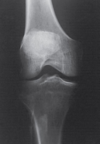

Describe the brightness of this image

Excessive brightness